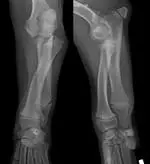

The puppy was sedated with xylazine, glycopyrrolate, and nalbuphine intravenously, and orthogonal radiographs of the left and right antebrachii were obtained. Radiographs of the right radius and ulna were normal. However, radiographs of the left antebrachium revealed caudolateral displacement of the radial head with normal positioning of the humeroulnar joint (Figure 1).

Figure 1: Orthogonal radiographs of the left antebrachium showing caudolateral displacement of the radial head